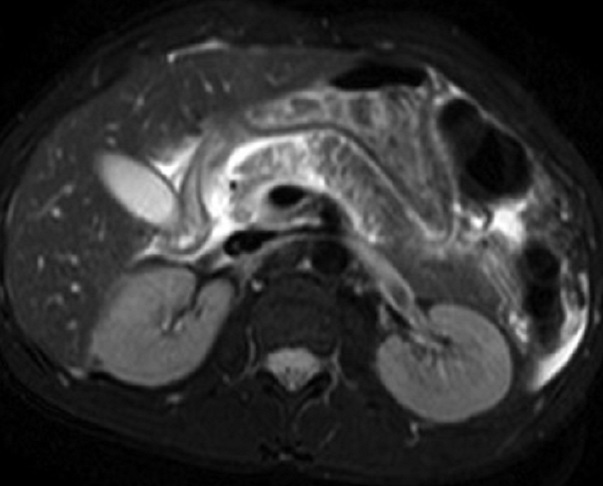

Image radiologique IRM

d'une trauma du pancreas avec aspect elargissement a

hypersignal heterogene du corp pancreas . Image IRM

pondere T2 coupe axiale . |